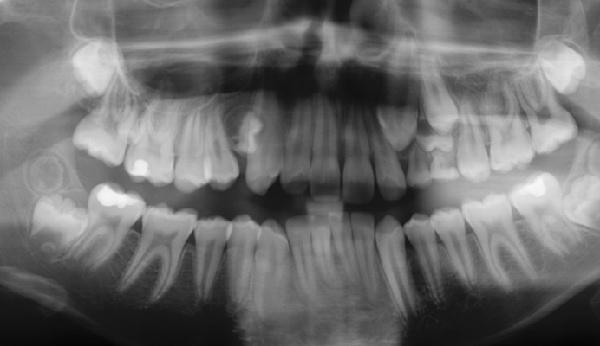

Présentes en germe dès l’âge de 12 ans, les dents de sagesse se constituent durant l’adolescence. On les appelle les troisièmes molaires. Elles se situent tout au fond de la bouche et sont les dernières à apparaître. Les dents d...